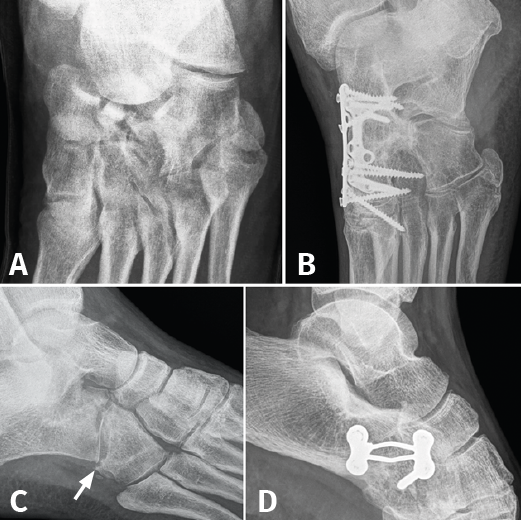

Figura 3. A: fractura de escafoides con luxación de la articulación de Chopart; B: artrodesis de la columna medial; C: fractura de cuboides “en cascanueces” (nutcracker’s fracture); D: artrodesis calcaneocuboidea.

Finalmente, 10 casos (40%) requirieron cirugía: 3 (12%) en el momento agudo (2 fracturas del cuerpo del calcáneo con afectación de la articulación subastragalina, que necesitaron reparación articular y osteosíntesis, y 1 caso por fractura de escafoides con luxación de Chopart, que requirió artrodesis de la columna medial). Por otro lado, en 7 casos (28%) se realizó cirugía de reconstrucción secundaria, mas allá de los 2 meses del traumatismo inicial (3 casos de artrodesis calcaneocuboidea, 3 casos de artrodesis de Lisfranc y 1 caso de artrodesis tibiotalocalcánea). Cabe mencionar que, de los 3 casos en los que se realizó artrodesis calcaneocuboidea, 2 necesitaron reintervención quirúrgica: uno por pseudoartrosis, relizándose nueva artrodesis con injerto de cresta ilíaca, y otro por inestabilidad de las articulaciones vecinas, terminando finalmente en panartrodesis (Figura 3).